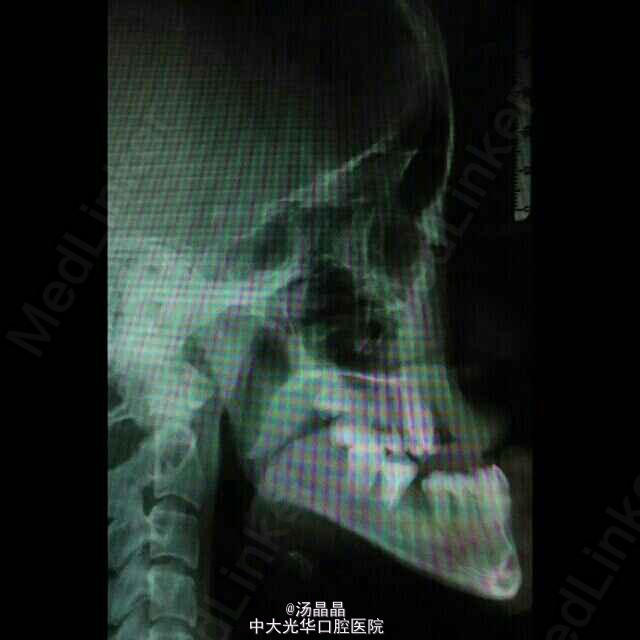

患者青年女性,上颌后缩,下颌前突6年,随发育渐进加重

面下三分之一长面型,侧面严重凹面型,上颌后缩,下颌前突,双侧颞下颌动度一致,无压痛,未闻及弹响和杂音,全口牙齿见正畸托槽,16.11.21.25.36.46缺失,中线齐,全牙弓反合,反覆盖大于3cm